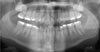

Adult with Root Resorption – How Much Resorption is Too Much to Retreat?

Case number: 154378

This patient really just wants cosmetic alignment but this Townie's biggest concern is the existing root resorption. What would you do?